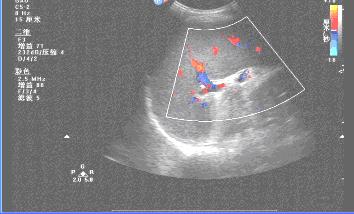

二、慢性肝炎纤维化时超声影像的表现:

肝回声增粗,肝内血管走行不规则,脾大。